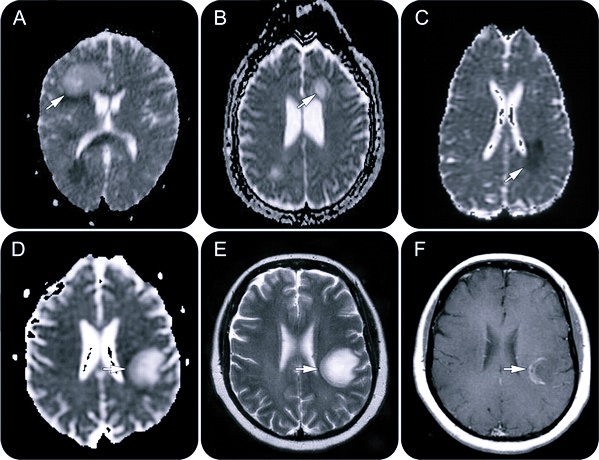

- МРТ – магнитная томограмма показывает гиперсигнальные очаги в белом веществе головного и спинного мозга на изображениях Т2 и гипосигнальные очаги – на Т1 (количество коррелирует с тяжестью заболевания);

Как выглядят очаги демиелинизации?

В спинном мозге очаги демиелинизации выглядят как удлиненные образования, распространяющиеся из центра на периферию с вовлечением в патологический процесс задних рогов. Конечным этапом прогрессирования поражения при рассеянном склерозе являются “черные дыры”, свидетельствующие о деструкции аксонов.